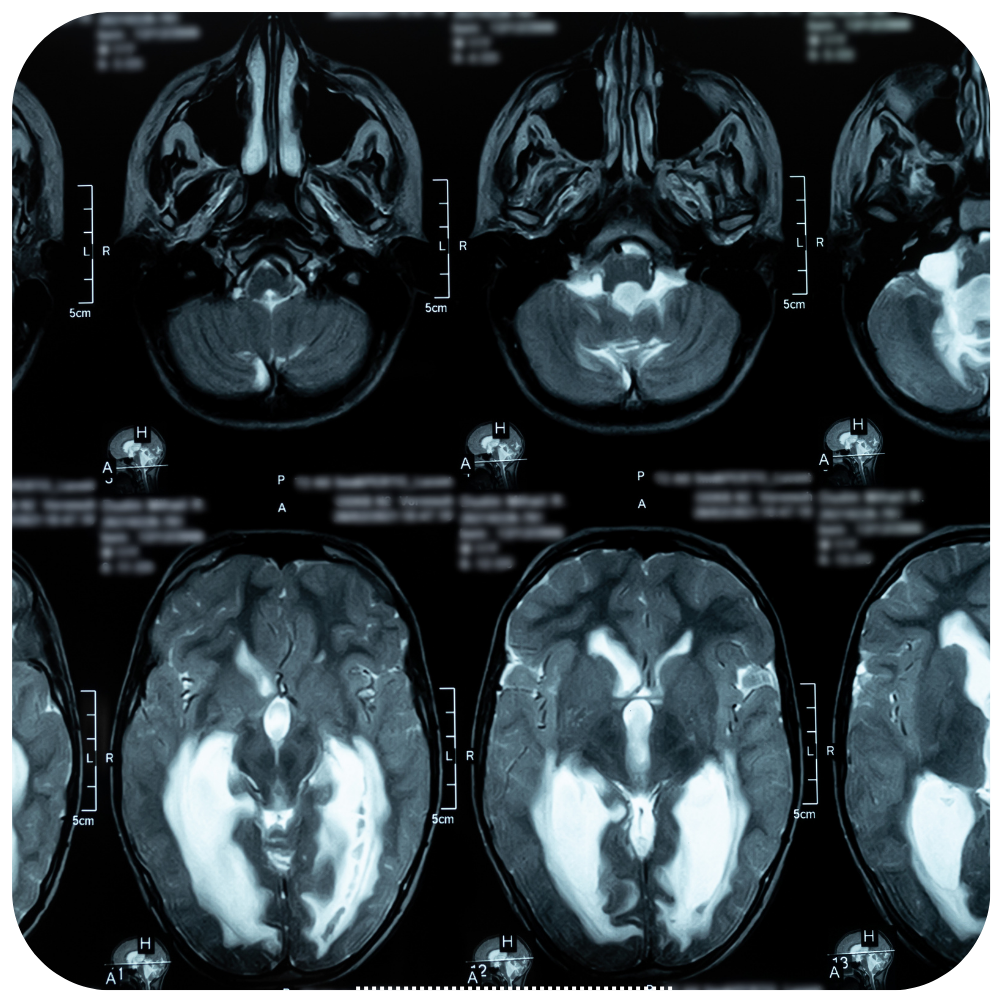

Hidrocefalia congénita

Hidrocefalia congénita. Acumulación de liquido en las cavidades del cerebro el cual hace que aumente la presión intracraneal y puede ocasionar daño cerebral.

Su tratamiento consiste en la derivación del líquido hacia otra cavidad, generalmente peritoneal, mediante la colocación de una sonda de derivación.